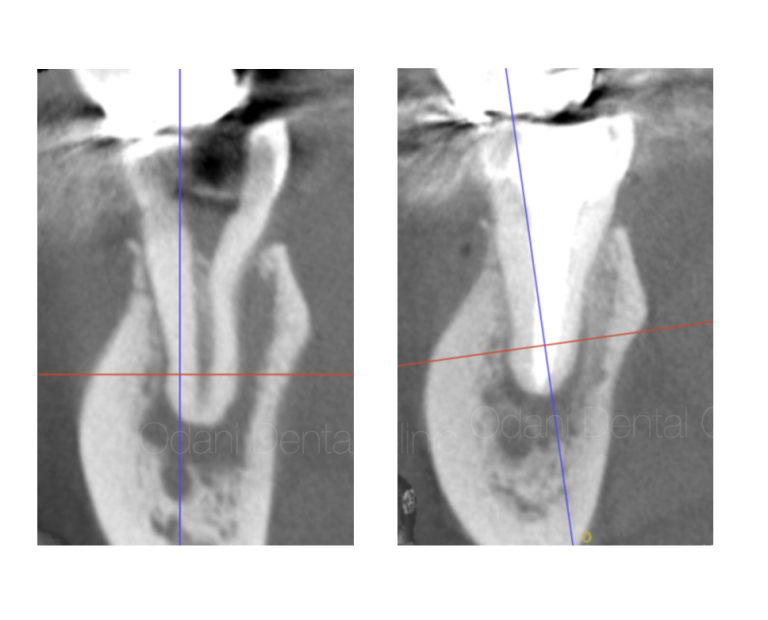

CTとマイクロスコープにより隠れた根管を発見して治療した症例 1年経過

症例プロフィール 来院までの背景 最近奥歯が噛むと違和感があるということで健診希望のため来院されまし...